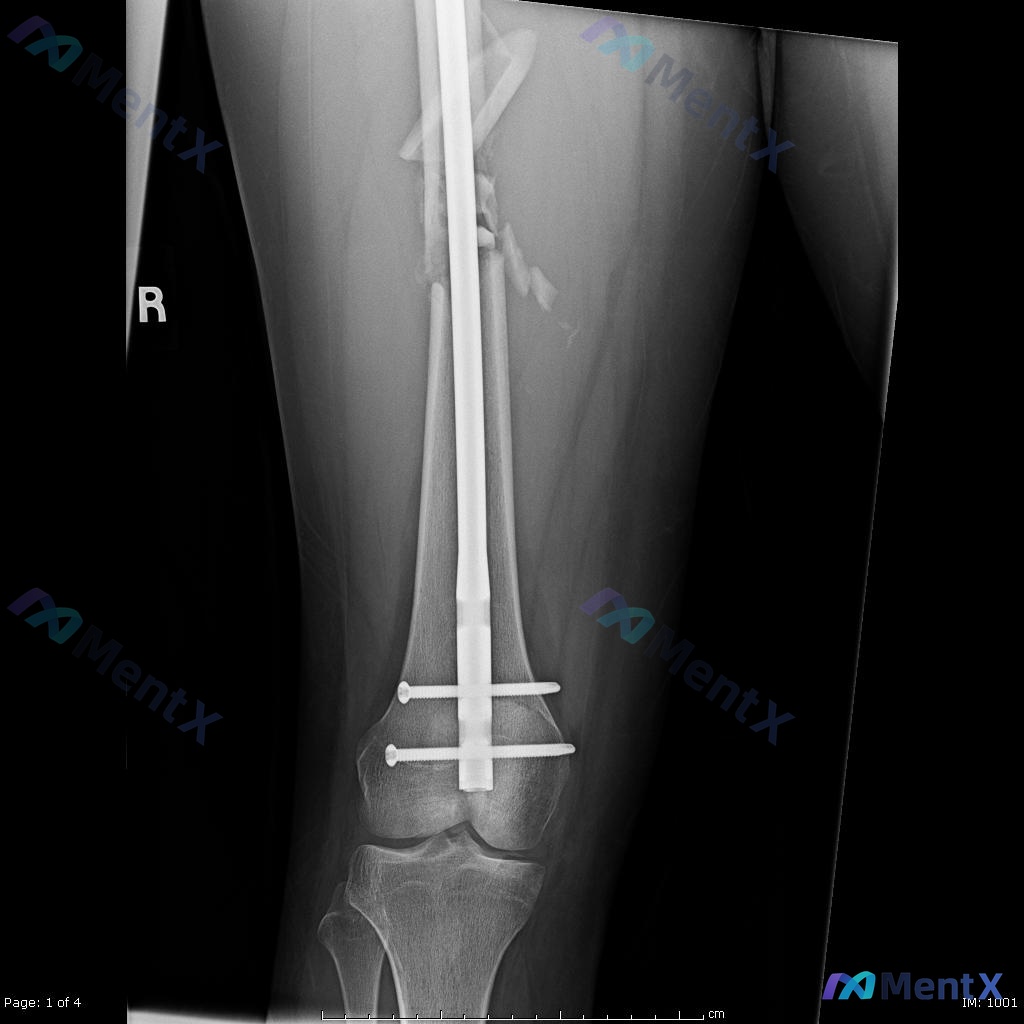

- 术后(图C/D):已行12mm髓内钉内固定(从大转子插至膝关节上方),远端两枚横向锁钉固定;内固定物形态完整、位置良好;骨折端大致对位,粉碎骨块被髓内钉包容